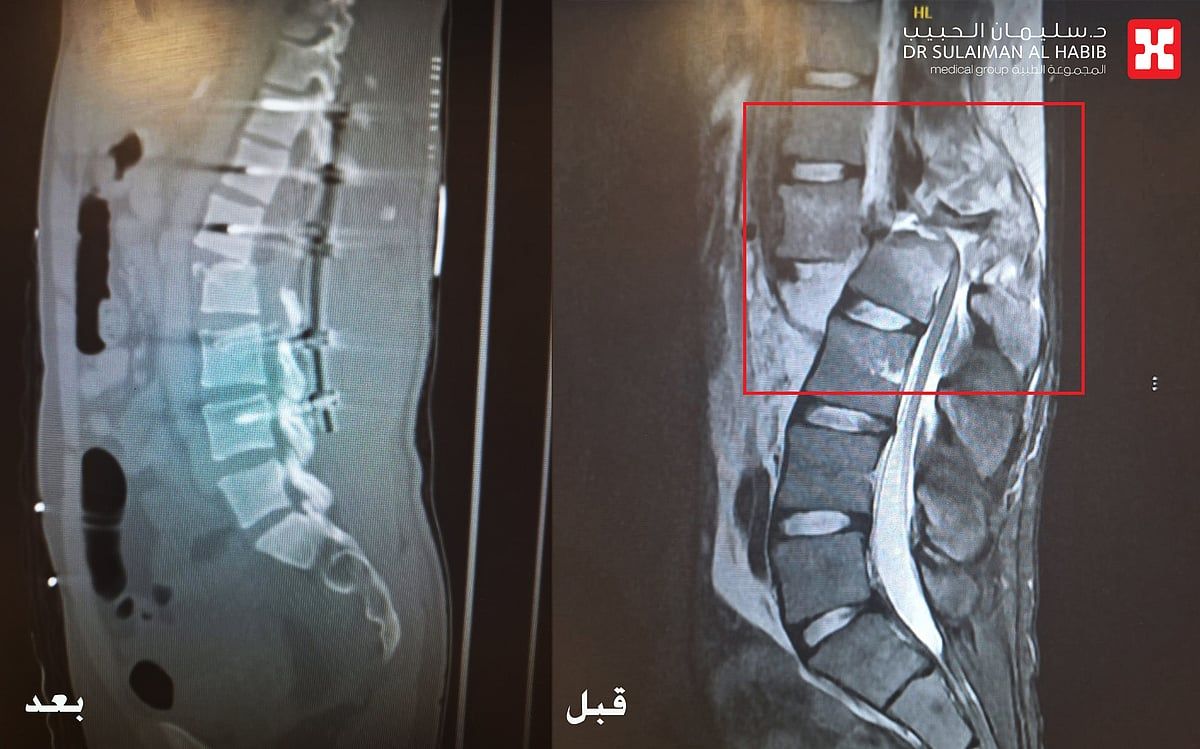

والذي أضاف بأن المراجع وصل قسم الطوارىء بالمستشفى عبر الهلال الأحمر، عقب إصابته بالحادث، يعاني من آلاماً شديدة وإصابات متعددة في الوجه والبطن والأطراف وتورمات في كامل الجسم. على الفور تم تقديم الإسعافات الأولية وإجراء فحوصات بأشعة الرنين المغناطيسي (M.R.I) والأشعة المقطعية (C.T Scan) والأشعة السينية الرقمية (Digital X-rays)، والتي بينت وجود كسر في الفقرة القطنية الأولى وتحطم عظم الفقرة الثانية من الخلف (L1-L2)، وكذلك نزوح الفقرات وإنضغاطها وتغير مكانها نتيجة قوة الحادث، بالإضافة إلى وجود قطع وتهتك في غشاء الأعصاب بالعمود الفقري، الأمر الذي أدى لشلل كامل الأطراف السفلية.

موضحاً أن الفريق الطبي المكون من استشاريي جراحة العمود الفقري والمخ والأعصاب، والطوارىء والعناية المركزة والتخدير، عقب دراستهم للحالة إتخذوا القرار بالتدخل الجراحي العاجل، حيث تم نقل المراجع مباشرة إلى قسم العمليات، مفيداً بأن العملية استغرقت 7 ساعات متواصلة تحت التخدير العام، وتم فيها إعادة فقرات العمود الفقري إلى موضعها الصحيح وإصلاح الفقرة الثانية القطنية، ومعالجة غشاء الأعصاب كلياً، تبع ذلك إعادة الأعصاب المصابة إلى مكانها الطبيعي بصعوبة شديدة، نقل بعدها الى العناية المركزة (I.C.U).